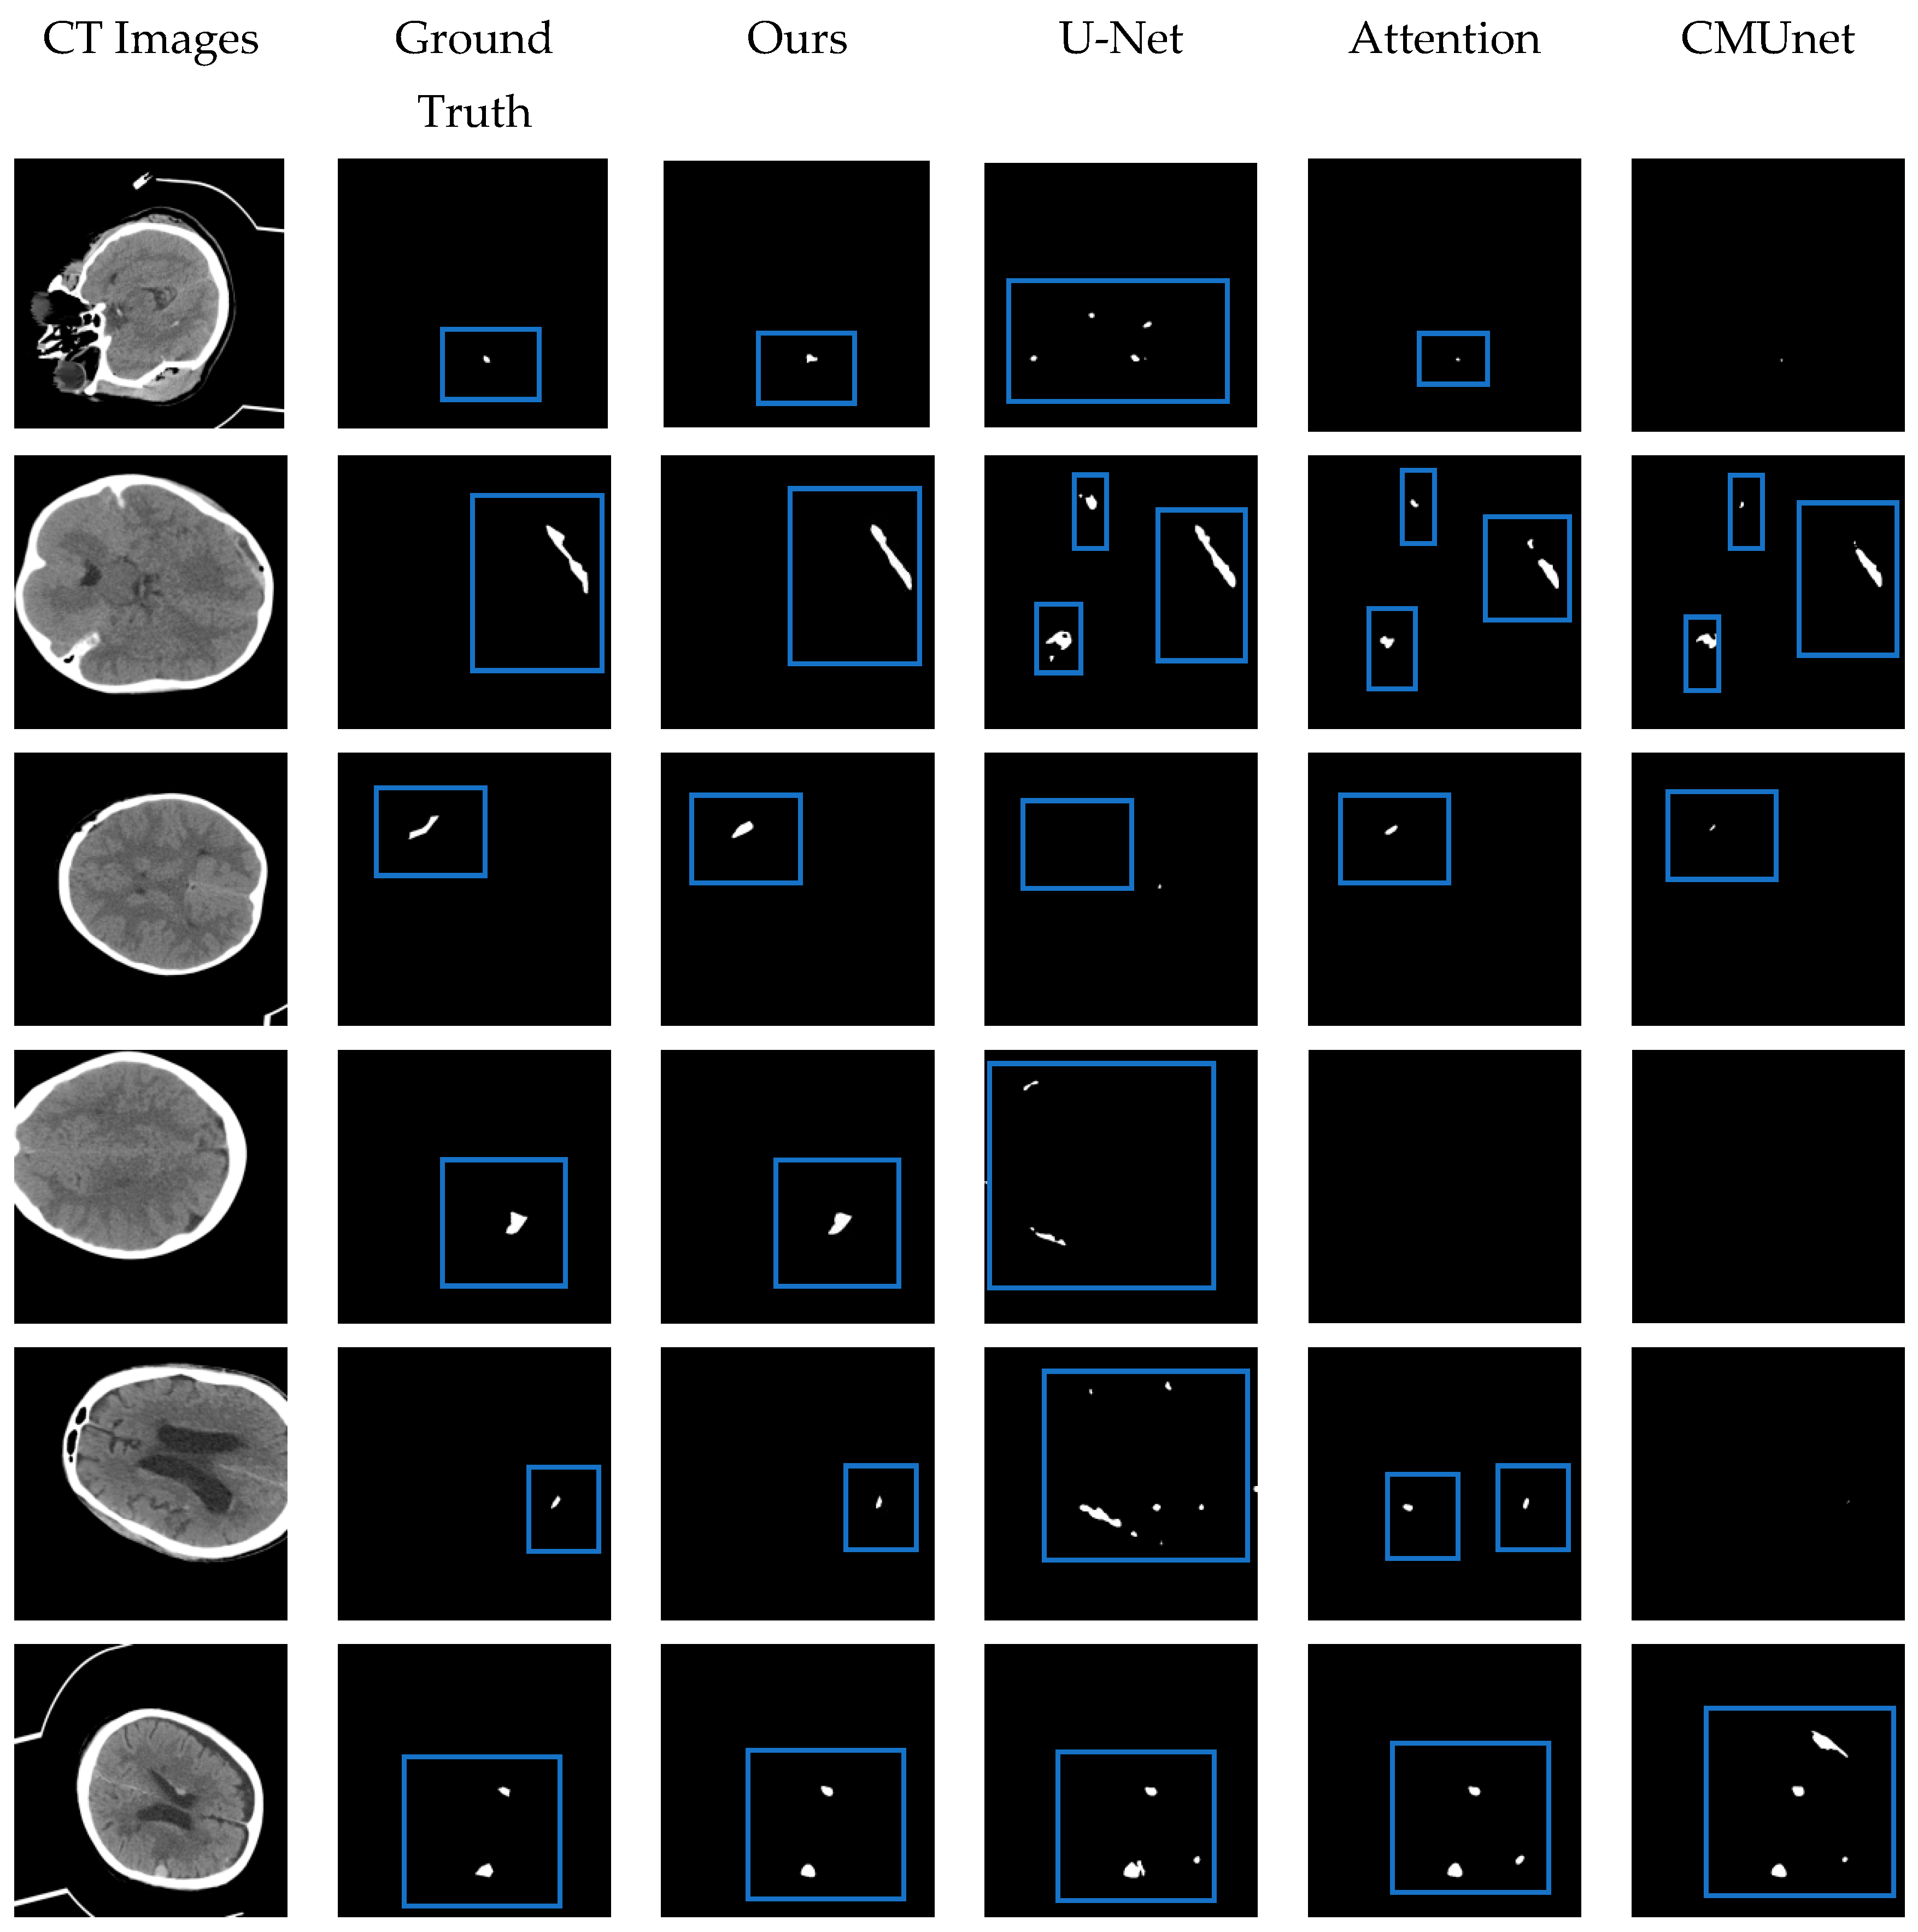

| Name | Dice | Jaccard | Sensitivity | Precision |

|---|---|---|---|---|

| Hssayeni et al. [32] | 0.315 | 0.218 | ||

| U-Net [25] | 0.610 | 0.491 | 0.644 | 0.632 |

| Attention U-Net [27] | 0.645 | 0.529 | 0.667 | 0.676 |

| CMUNet [40] | 0.666 | 0.547 | 0.656 | 0.707 |

| Ours | 0.717 | 0.596 | 0.779 | 0.712 |

4.5. Comparison with Other Methods